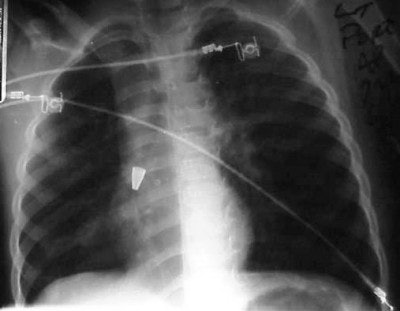

In figure 6 we have a 24-month-old who has been intubated, with a diagnosis of RSV. The film is slightly overpenetrated as we cannot clearly make out lung markings, but we can see the bronchial air shadow and the tip of the ETT (marker arrow), which is right at the carina (the bifurcation of the right and left mainstem bronchus). Doctors attempted to re-position the ETT and the left lung is ruptured causing a tension pneumothorax (arrow, figure 7).

In figure 8, the radiographic technique has been adjusted to show lung markings after the placement of a chest tube on the left. The chest tube, however, appears to be abutting the ETT, and notice the air shadow extending around the pericardium and along the diaphragm, consistent with the diagnoses of pneumomediastinum.